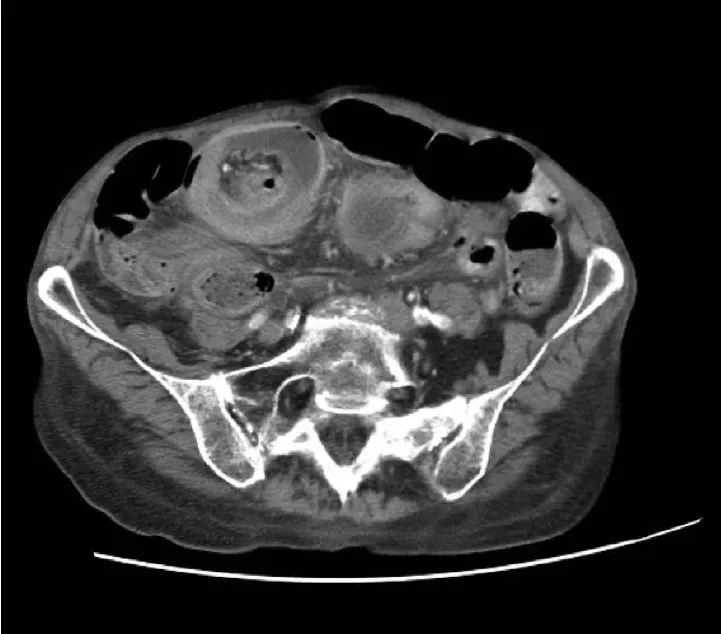

E4. CT – 드물게 사용, 주로 성인이나 lead point 평가 시

초음파는 진단에 가장 적합한 영상 검사법이며, 타겟 사인(target sign) 또는 **가성신장 사인(pseudokidney sign)**을 평가할 수 있습니다.

단순 복부 X-ray는 복막염 또는 장 천공 여부를 확인하는 데 사용할 수 있지만, 장중첩증을 배제하는 용도로는 적절하지 않습니다.